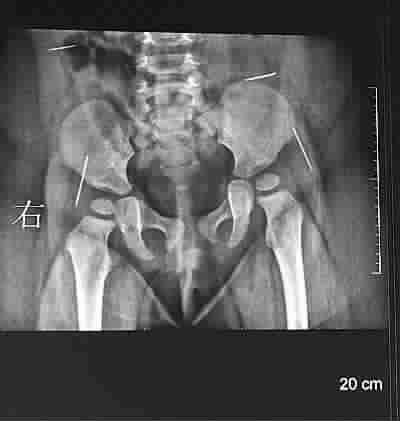

■ X片显示,女婴体内有四根针状金属物 图 TP

原来7月22日,由于小雨欣一直哭闹,家人在哄她睡觉时在其臀部发现了一根没有针鼻的缝衣针,于是带孩子到淮安市第一人民医院就诊,医生在为小雨欣做X光检查时发现,其体内还有四根针状金属物,遂建议到市妇幼保健院做手术。